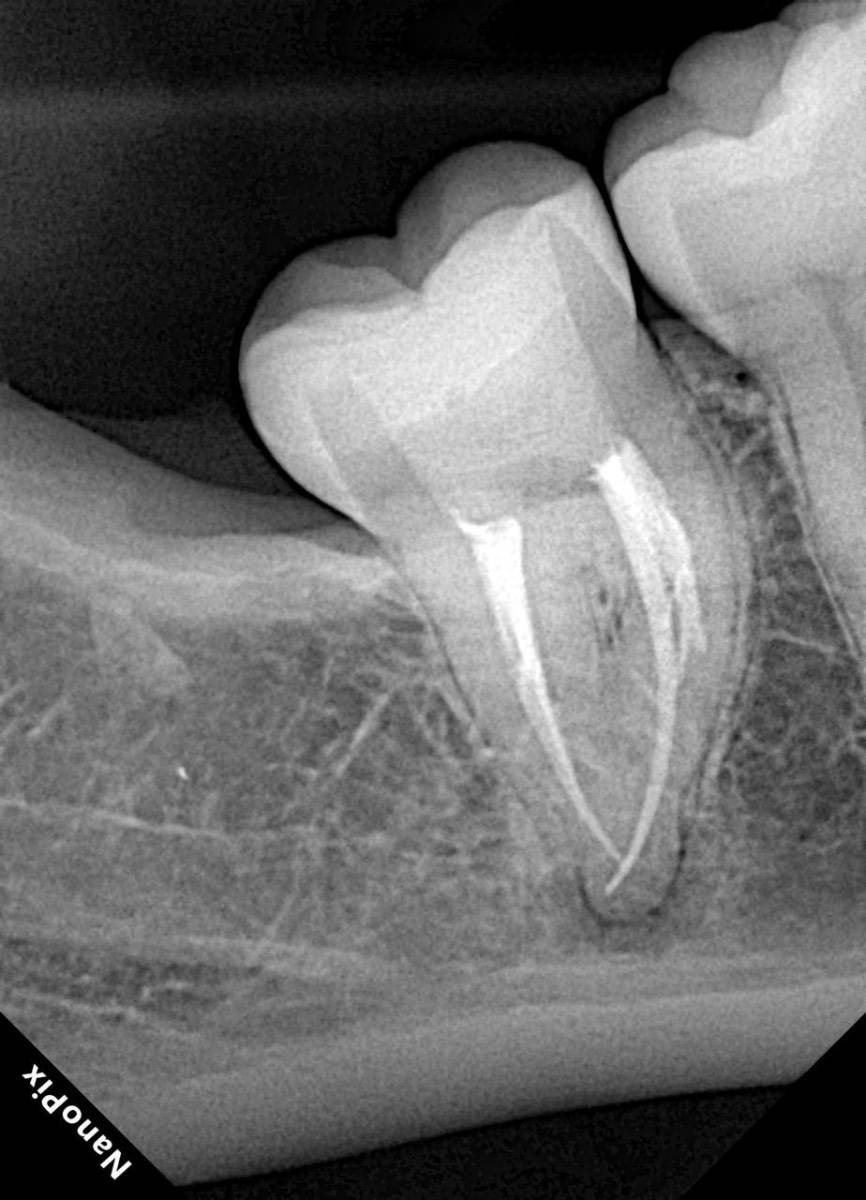

Гарриевич Опубликовано 31 января Автор Поделиться Опубликовано 31 января Когда в твоем кресле оказывается пациент с редким заболеванием «стоматолог-терапевт» работать всегда… легче. Именно! Потому что ты на 100% уверен, что этот человек понимает разницу между «гарантия» и «прогноз», а он на 100% уверен, что ты тот кто ему нужен. Зуб 4.7 со сложной анатомией, ступенькой в мезиальной системе, двойным изгибом, пропущенным каналом и апикальным периодонтитом. Реколл 1 год И сам осмотр через 1 год 4 1 1 Ссылка на комментарий

Гарриевич Опубликовано 18 марта Автор Поделиться Опубликовано 18 марта В 13.03.2026 в 15:26, Doc сказал: Круто! То, что вынимается, доктору вернуть надо или в металлолом сдать? :))) Обычно мы сдаем в чернмет, какие никакие деньги)) Реколл 3 года 1 Ссылка на комментарий